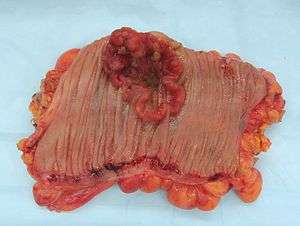

Macroscopy

Cancers on the right side of the large intestine (ascending colon and cecum) tend to be exophytic, that is, the tumor grows outwards from one location in the bowel wall. This very rarely causes obstruction of feces, and presents with symptoms such as anemia. Left-sided tumors tend to be circumferential, and can obstruct the bowel lumen, much like a napkin ring, and results in thinner caliber stools.

Macroscopy

Appearance of the inside of the colon showing one invasive colorectal carcinoma (the crater-like, reddish, irregularly shaped tumor)

Appearance of the inside of the colon showing one invasive colorectal carcinoma (the crater-like, reddish, irregularly shaped tumor) Gross appearance of a colectomy specimen containing two adenomatous polyps (the brownish oval tumors above the labels, attached to the normal beige lining by a stalk) and one invasive colorectal carcinoma (the crater-like, reddish, irregularly shaped tumor located above the label)

Gross appearance of a colectomy specimen containing two adenomatous polyps (the brownish oval tumors above the labels, attached to the normal beige lining by a stalk) and one invasive colorectal carcinoma (the crater-like, reddish, irregularly shaped tumor located above the label) Endoscopic image of colon cancer identified in sigmoid colon on screening colonoscopy in the setting of Crohn's disease